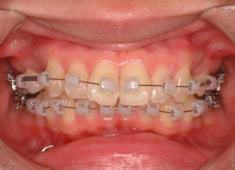

治療開始時

治療開始から1年7ヶ月後